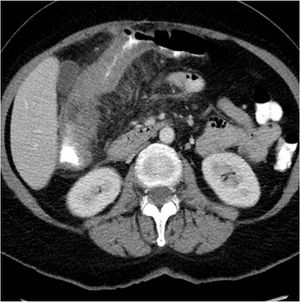

A 56-year-old female presented with abdominal pain, R/O colitis. There is a long segment of asymmetrical wall thickening seen involving the ascending colon just above the ileocaecal region to proximal third of transverse colon associated with luminal narrowing and significant surrounding fat stranding and enlarged regional lymph node.